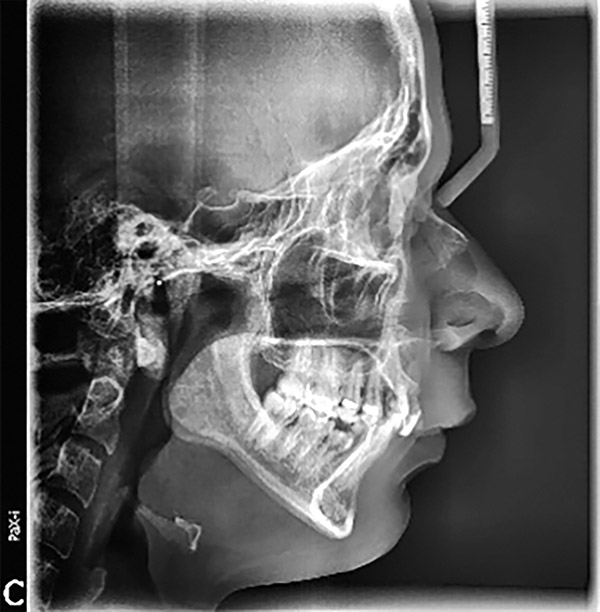

Se presenta un paciente de 25 años de edad. Radiográficamente se observa clase II esquelética, hiperdivergencia (Figura 1), en la fotografía extraoral de sonrisa el paciente se muestra con apiñamiento severo y la mordida profunda (Figura 2).

Figura 1. Radiografía lateral de cráneo.